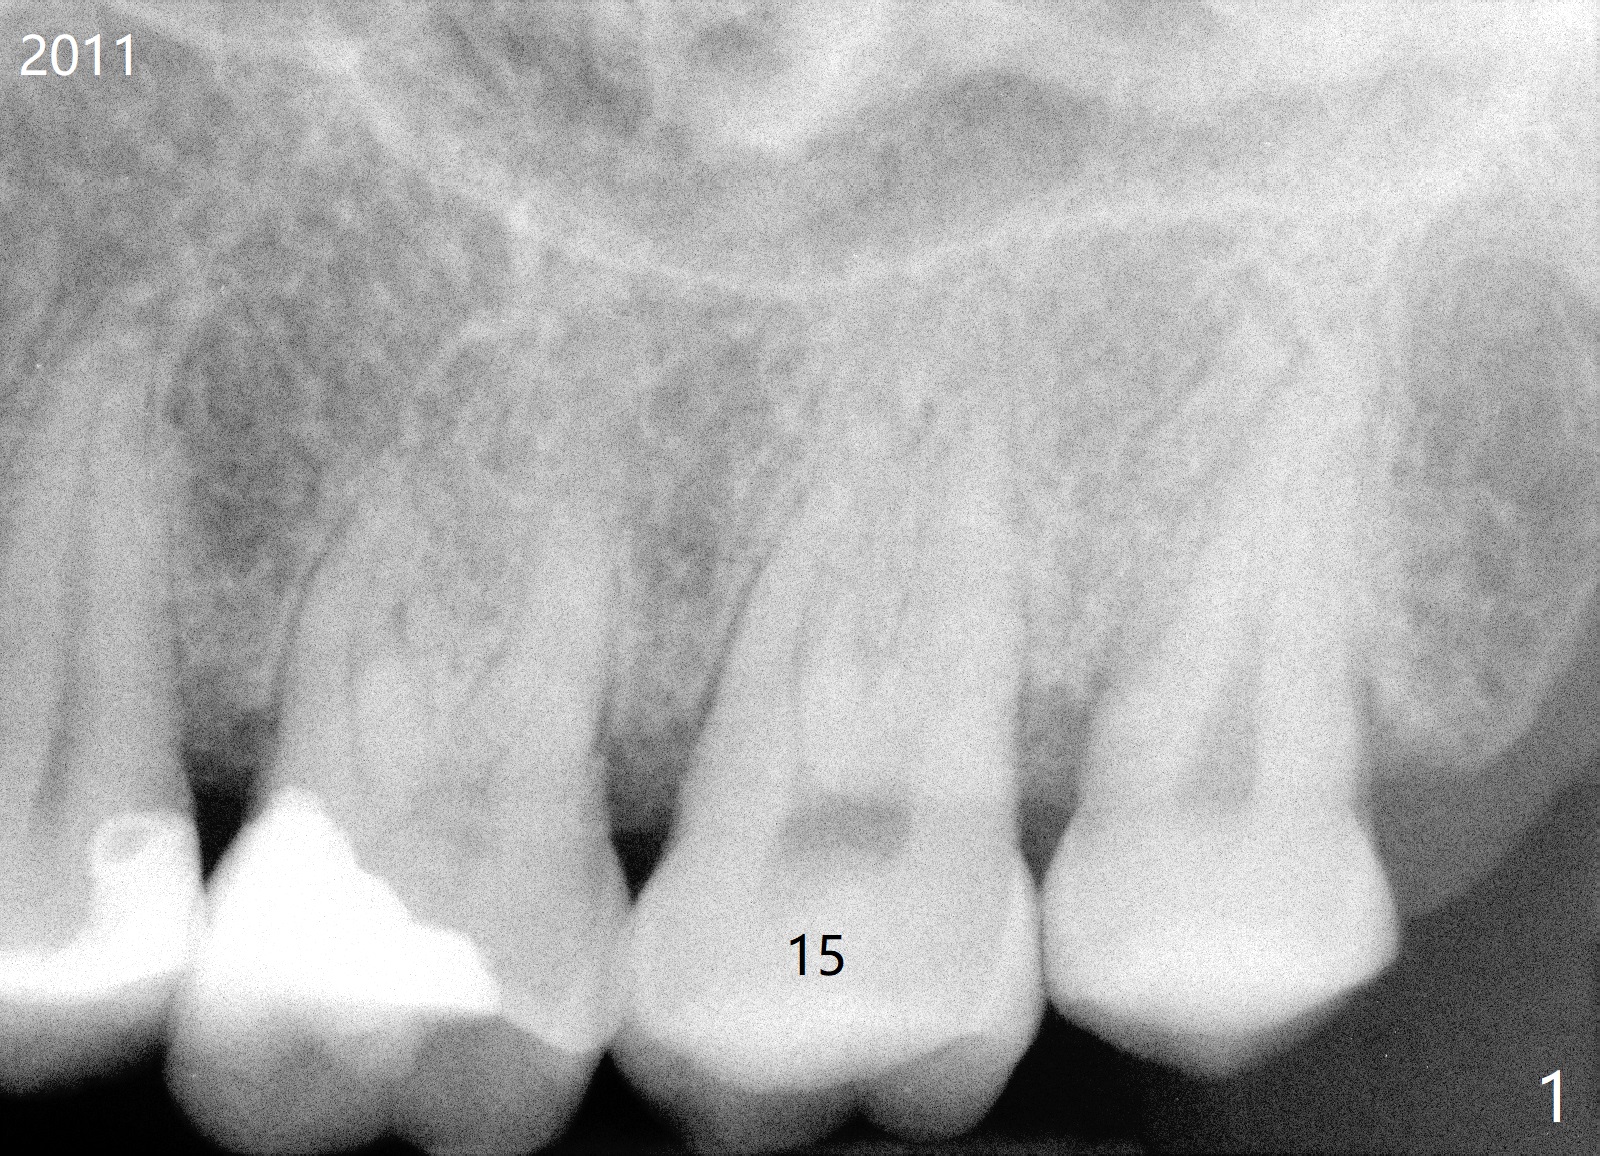

A 54-year-old woman has had palatal root fracture at #15 for several years (Fig.1,2) and finally accept extraction and immediate implant (Fig.3,4). For better trajectory and less screw loosening and crown fracture, guide will be fabricated.